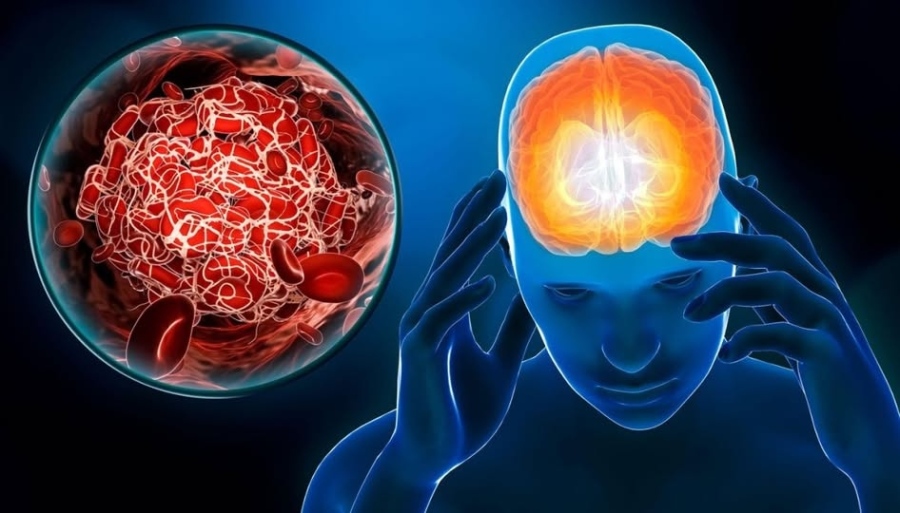

Община Враца се присъединява към националната инициатива на Асоциацията за инсулт и афазия (АИА), обявила 11 ноември за Национален ден за борба с инсулта.

Инициативата цели да повиши обществената информираност за инсулта и неговите последици, както и да насочи вниманието към нуждата от по-добра превенция, лечение и подкрепа за хората, преживели инсулт, и техните близки.